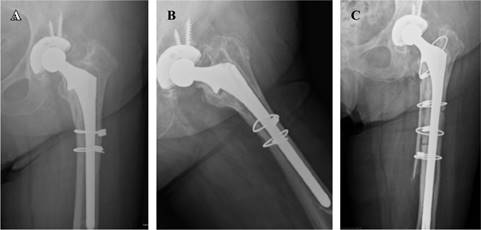

En todas se usó el abordaje posterolateral a la cadera. Realizamos una osteotomía trocantérica ampliada (OTA) en 19 casos (24.4%). La fijación de la osteotomía se realizó en todos los casos mediante cerclajes asociando en tres pacientes osteosíntesis con placa trocantérica y en 11 casos aloinjerto estructural criopreservado (Figura 1). En 42 casos se llevó a cabo de forma concomitante una revisión del componente acetabular, implantándose en 17 casos cotilos de doble movilidad, en 24 cotilos hemiesféricos monopolares y en un caso un cotilo retentivo.

Figura 1: Aflojamiento aséptico A) y B) recambiado por vástago con un diámetro y longitud mayor. Aloinjerto estructural con cerclajes para reparar de la osteotomía trocantérica C).